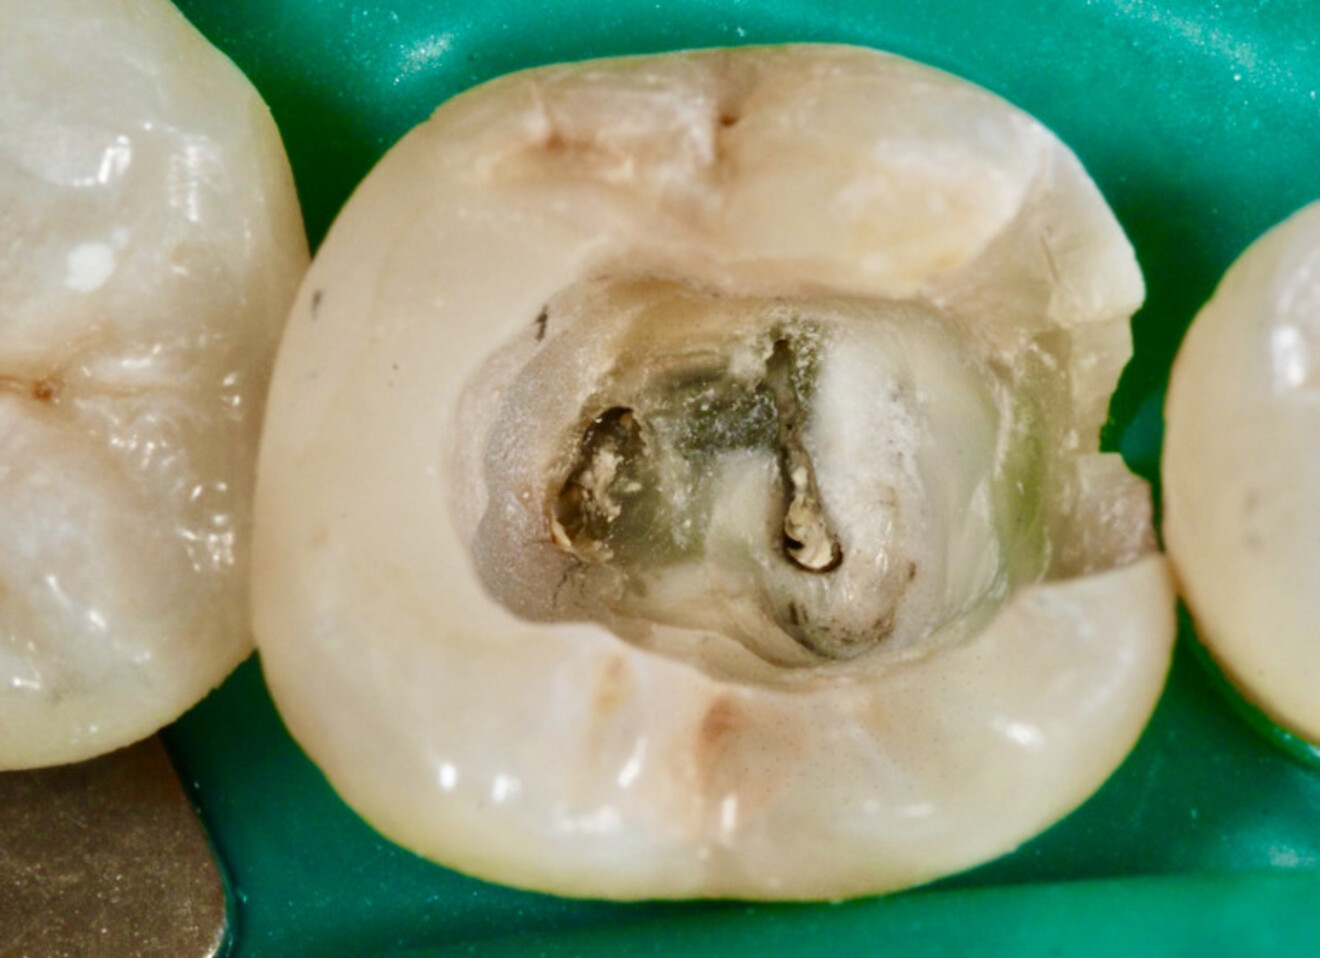

Fig. 2 : Contrôle radiographique en vue d’évaluer l’axe de délogement de la reconstitution corono-radiculaire, ce qui a permis de corriger l’angle de coupe.

D’un point de vue pratique, la première étape consiste à réduire les dimensions du tenon s’il occupe une grande partie de la structure coronaire, de préférence en lui donnant une forme cylindrique similaire à celle d’un tenon préfabriqué. De même, une reconstitution corono-radiculaire coulée ancrée dans plusieurs canaux doit d’abord être sectionnée jusqu’au niveau du plancher de la cavité pulpaire, afin de la traiter comme un ensemble de tenons unitaires, ce qui diminue le degré de rétention global du système. La réduction du tenon doit être effectuée avec des fraises en carbure spécialement conçues pour découper le métal, sous une irrigation abondante. Les évaluations cliniques et radiographies préliminaires sont essentielles pour planifier l’angle de coupe. La procédure doit être fréquemment vérifiée et, si nécessaire, il convient d’effectuer des contrôles radiographiques avant qu’une quantité excessive de dentine ne soit sacrifiée (Figs. 1–3).